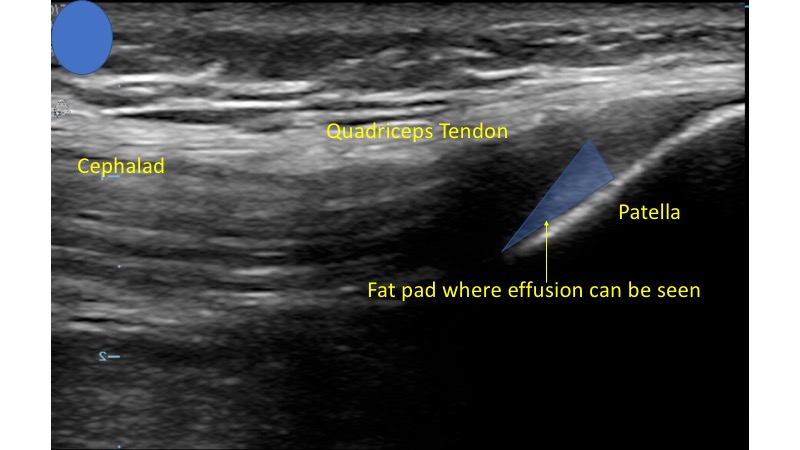

- In this view you should be able to identify the quadriceps tendon attached to the patella.

- Deep to the tendon and proximal to the patella you should be able to identify the suprapatellar fat pad superficial to the femur. (Fig. 4)

- This will be displaced by joint effusion when a significant amount of fluid exists in this space.4 (Video 1)